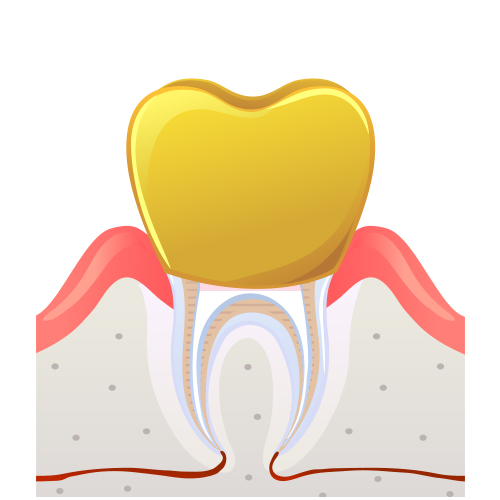

신경치료란?

치아의 신경에 손상 및 감염이 발생한 경우, 신경을 제거하고

생체친화적인 재료를 채워 치아가 기능을 유지할 수 있게 만들어주는 치료입니다.

신경관 영구재료로 채움

치아등 머리부분을 레진으로 채우거나 기둥을 만듦

07

씌우기 전 삭제

보철을 씌움 신경치료완료